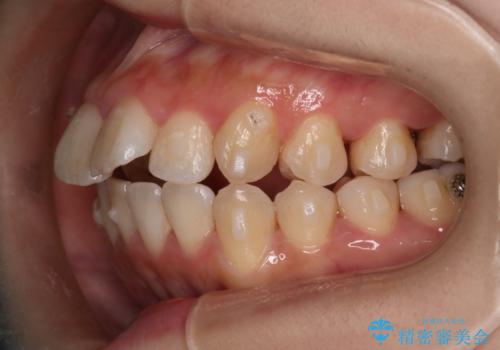

【インビザライン】マウスピースで開咬改善

- 開咬を主訴に来院されました。

IPR(歯と歯の間を削る処置)と顎間ゴムを行いながら、インビザラインで開咬を治療する計画を立てました。

治療をしながら、MFT(口腔筋機能療法)も行っていくことにしました。

歯の移動量が多いケースでしたが、患者様にマウスピースの使用とゴム掛けを頑張っていただいたので

リファイメント1回のみで治療を終わることができました。